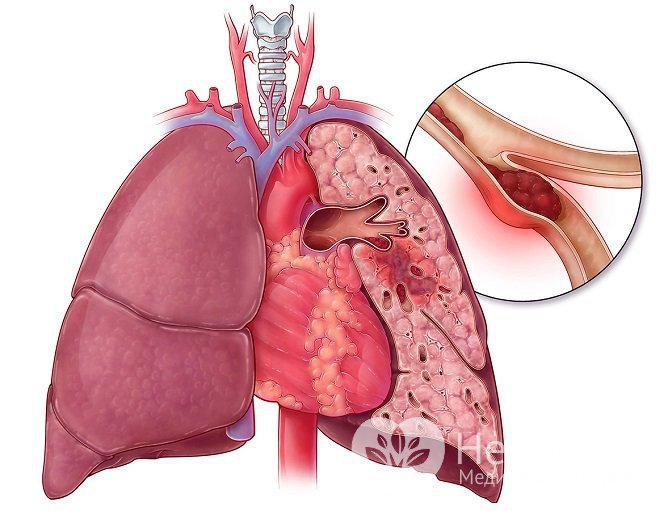

Инфаркт легкого – одна из наиболее опасных форм заболевания. Оно характеризуется быстрой гибелью клеток органа из-за внезапно прекратившегося кровообращения. Болезнь начинается внезапно, стремительно прогрессирует и чревата серьезными осложнениями.

Прекращение кровотока по ветви легочной артерии приводит к развитию легочного инфаркта

Прекращение кровотока по ветви легочной артерии приводит к развитию легочного инфарктаЧто это такое – инфаркт легкого?

Нарушение кровотока по легочной артерии вследствие ее сдавливания или закупорки приводит к кислородному голоданию клеток участка легкого, а впоследствии их гибели. Легкие обладают одной из наиболее развитых сосудистых сетей в организме и нуждаются в большом притоке крови. Блокирование притока в одном из сосудов приводит к системным нарушениям сердечно-сосудистой системы, вызывает повышение давления в малом круге кровообращения, может осложняться легочными кровотечениями и пневмонией. Легкое является одним из шоковых органов, то есть наиболее подверженных повреждению во время шоковых, терминальных состояний.

Что же происходит с тканью легкого, когда она недополучает кислород и питательные вещества? Альвеолоциты, клетки легкого, начинают отмирать, и образуется очаг некроза. На него реагирует иммунная система, стимулирующая выработку антител. В результате некроз осложняется аутоиммунным воспалением, в который вовлекается участок легочной ткани, с чем связаны осложнения и без того тяжелого заболевания.

Инфаркт бывает ишемическим, то есть вызванным ишемией – недостаточным поступлением крови в ткани, и геморрагическим, связанным с кровоизлиянием в паренхиму легкого, как следствие, сдавливания легочной ткани.